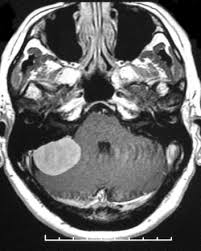

differential diagnosis